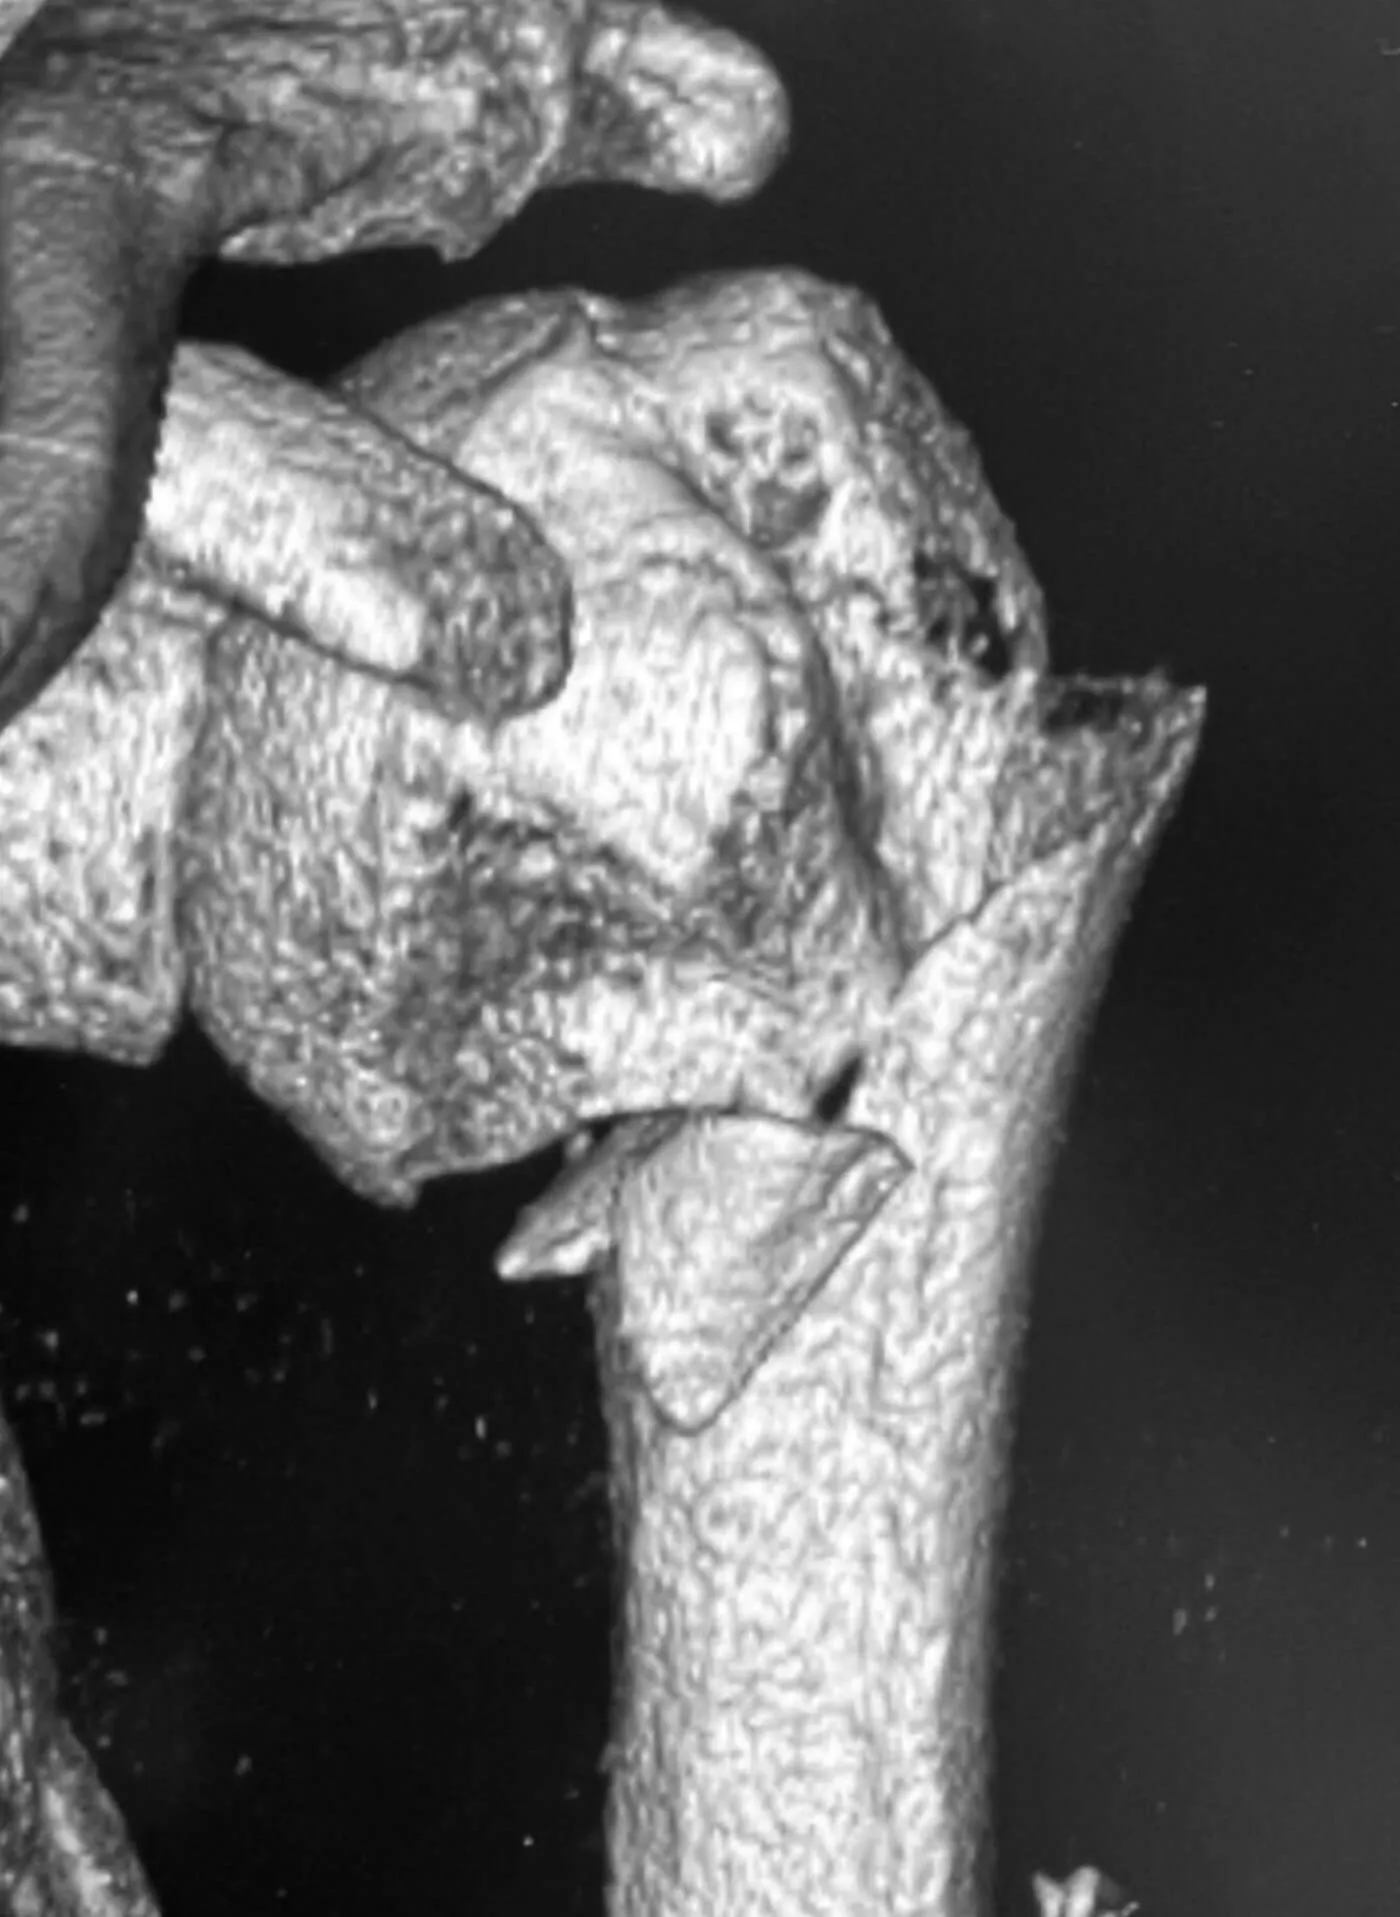

Przed operacją

Złamanie bliższego końca kości ramiennej

Pacjentka, lat 76, doznała złamania w wyniku upadku z wysokości własnej. Złamanie miało charakter wieloodłamowy ze znacznym przemieszczeniem kątowym odłamów. Bez leczenia operacyjnego chora nie odzyskałaby dobrego zakresu ruchomości i siły mięśniowej.